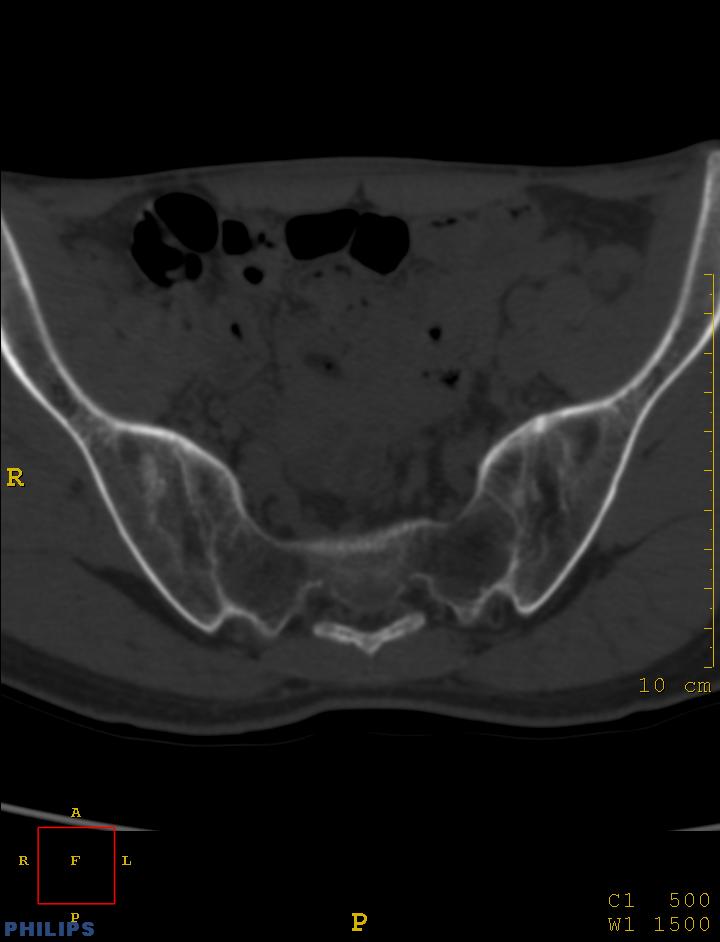

标题: CT14032:M34Y,双侧骶髂关节

m,34岁,腰痛三年,腰椎活动度明显减低,x片示腰椎竹节样改变

双侧骶髂关节面融合;强直脊柱炎

双侧骶髂关节骨性融合,软骨下囊性变,结合脊柱竹节样改变,典型的强直性脊柱炎。